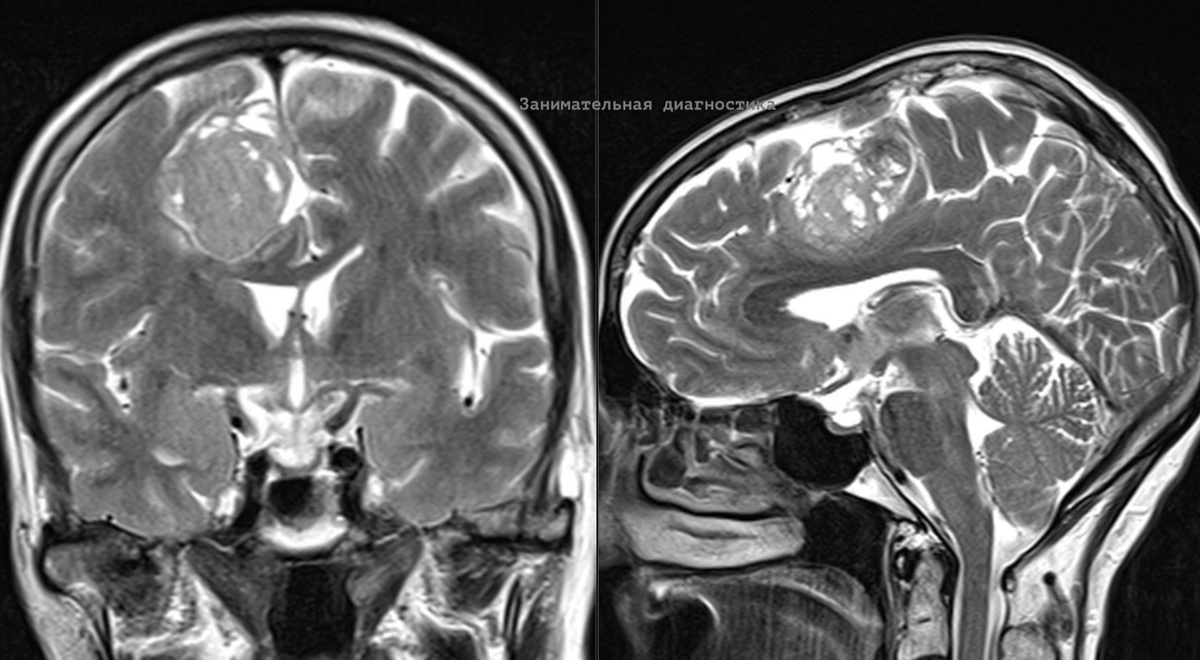

К нам на МРТ обратилась женщина 70 лет у которой ранее обнаружили опухоль на КТ. В таких случаях МРТ назначается для уточнения структуры опухоли и уточнения некоторых других нюансов (для решения по дальнейшей тактике). Образование достаточно крупное, размером с куриное яйцо, оказывает умеренное объёмное воздействие на мозг (масс-эффект). В таких ситуациях рекомендуется выполнение исследования с в/в контрастом. Это позволяет точнее оценить структуру опухоли и часто даже предположить её гистологический тип, что ранее (до эры МРТ) было нереальной задачей. Накопление контрастного препарата интенсивное. Расположение опухоли (она прилежит к твердой мозговой оболочке) и другие признаки позволяют нам на 99% быть уверенным гистологическом типе опухоли, это - менингиома. Менингиомы — это опухоли, которые развиваются из клеток мозговых оболочек, окружающих головной и спинной мозг. Случай интересен ещё и тем, что этих образований у женщины оказалось сразу четыре (!), в разных локализациях. Одно из

Образование достаточно крупное, размером с куриное яйцо, оказывает умеренное объёмное воздействие на мозг (масс-эффект).

В таких ситуациях рекомендуется выполнение исследования с в/в контрастом. Это позволяет точнее оценить структуру опухоли и часто даже предположить её гистологический тип, что ранее (до эры МРТ) было нереальной задачей.

Накопление контрастного препарата интенсивное. Расположение опухоли (она прилежит к твердой мозговой оболочке) и другие признаки позволяют нам на 99% быть уверенным гистологическом типе опухоли, это - менингиома.

Случай интересен ещё и тем, что этих образований у женщины оказалось сразу четыре (!), в разных локализациях. Одно из них мы увидели только после контрастного усиления, слишком оно было мелким.

Учитывая пожилой возраст и крайне медленный рост таких опухолей, нейрохирургом было принято решение отказаться от операции и ограничиться наблюдением.

Спустя год на контрольном МРТ исследовании размеры образований практически не изменились (это к вопросу о том, насколько медленно они растут).